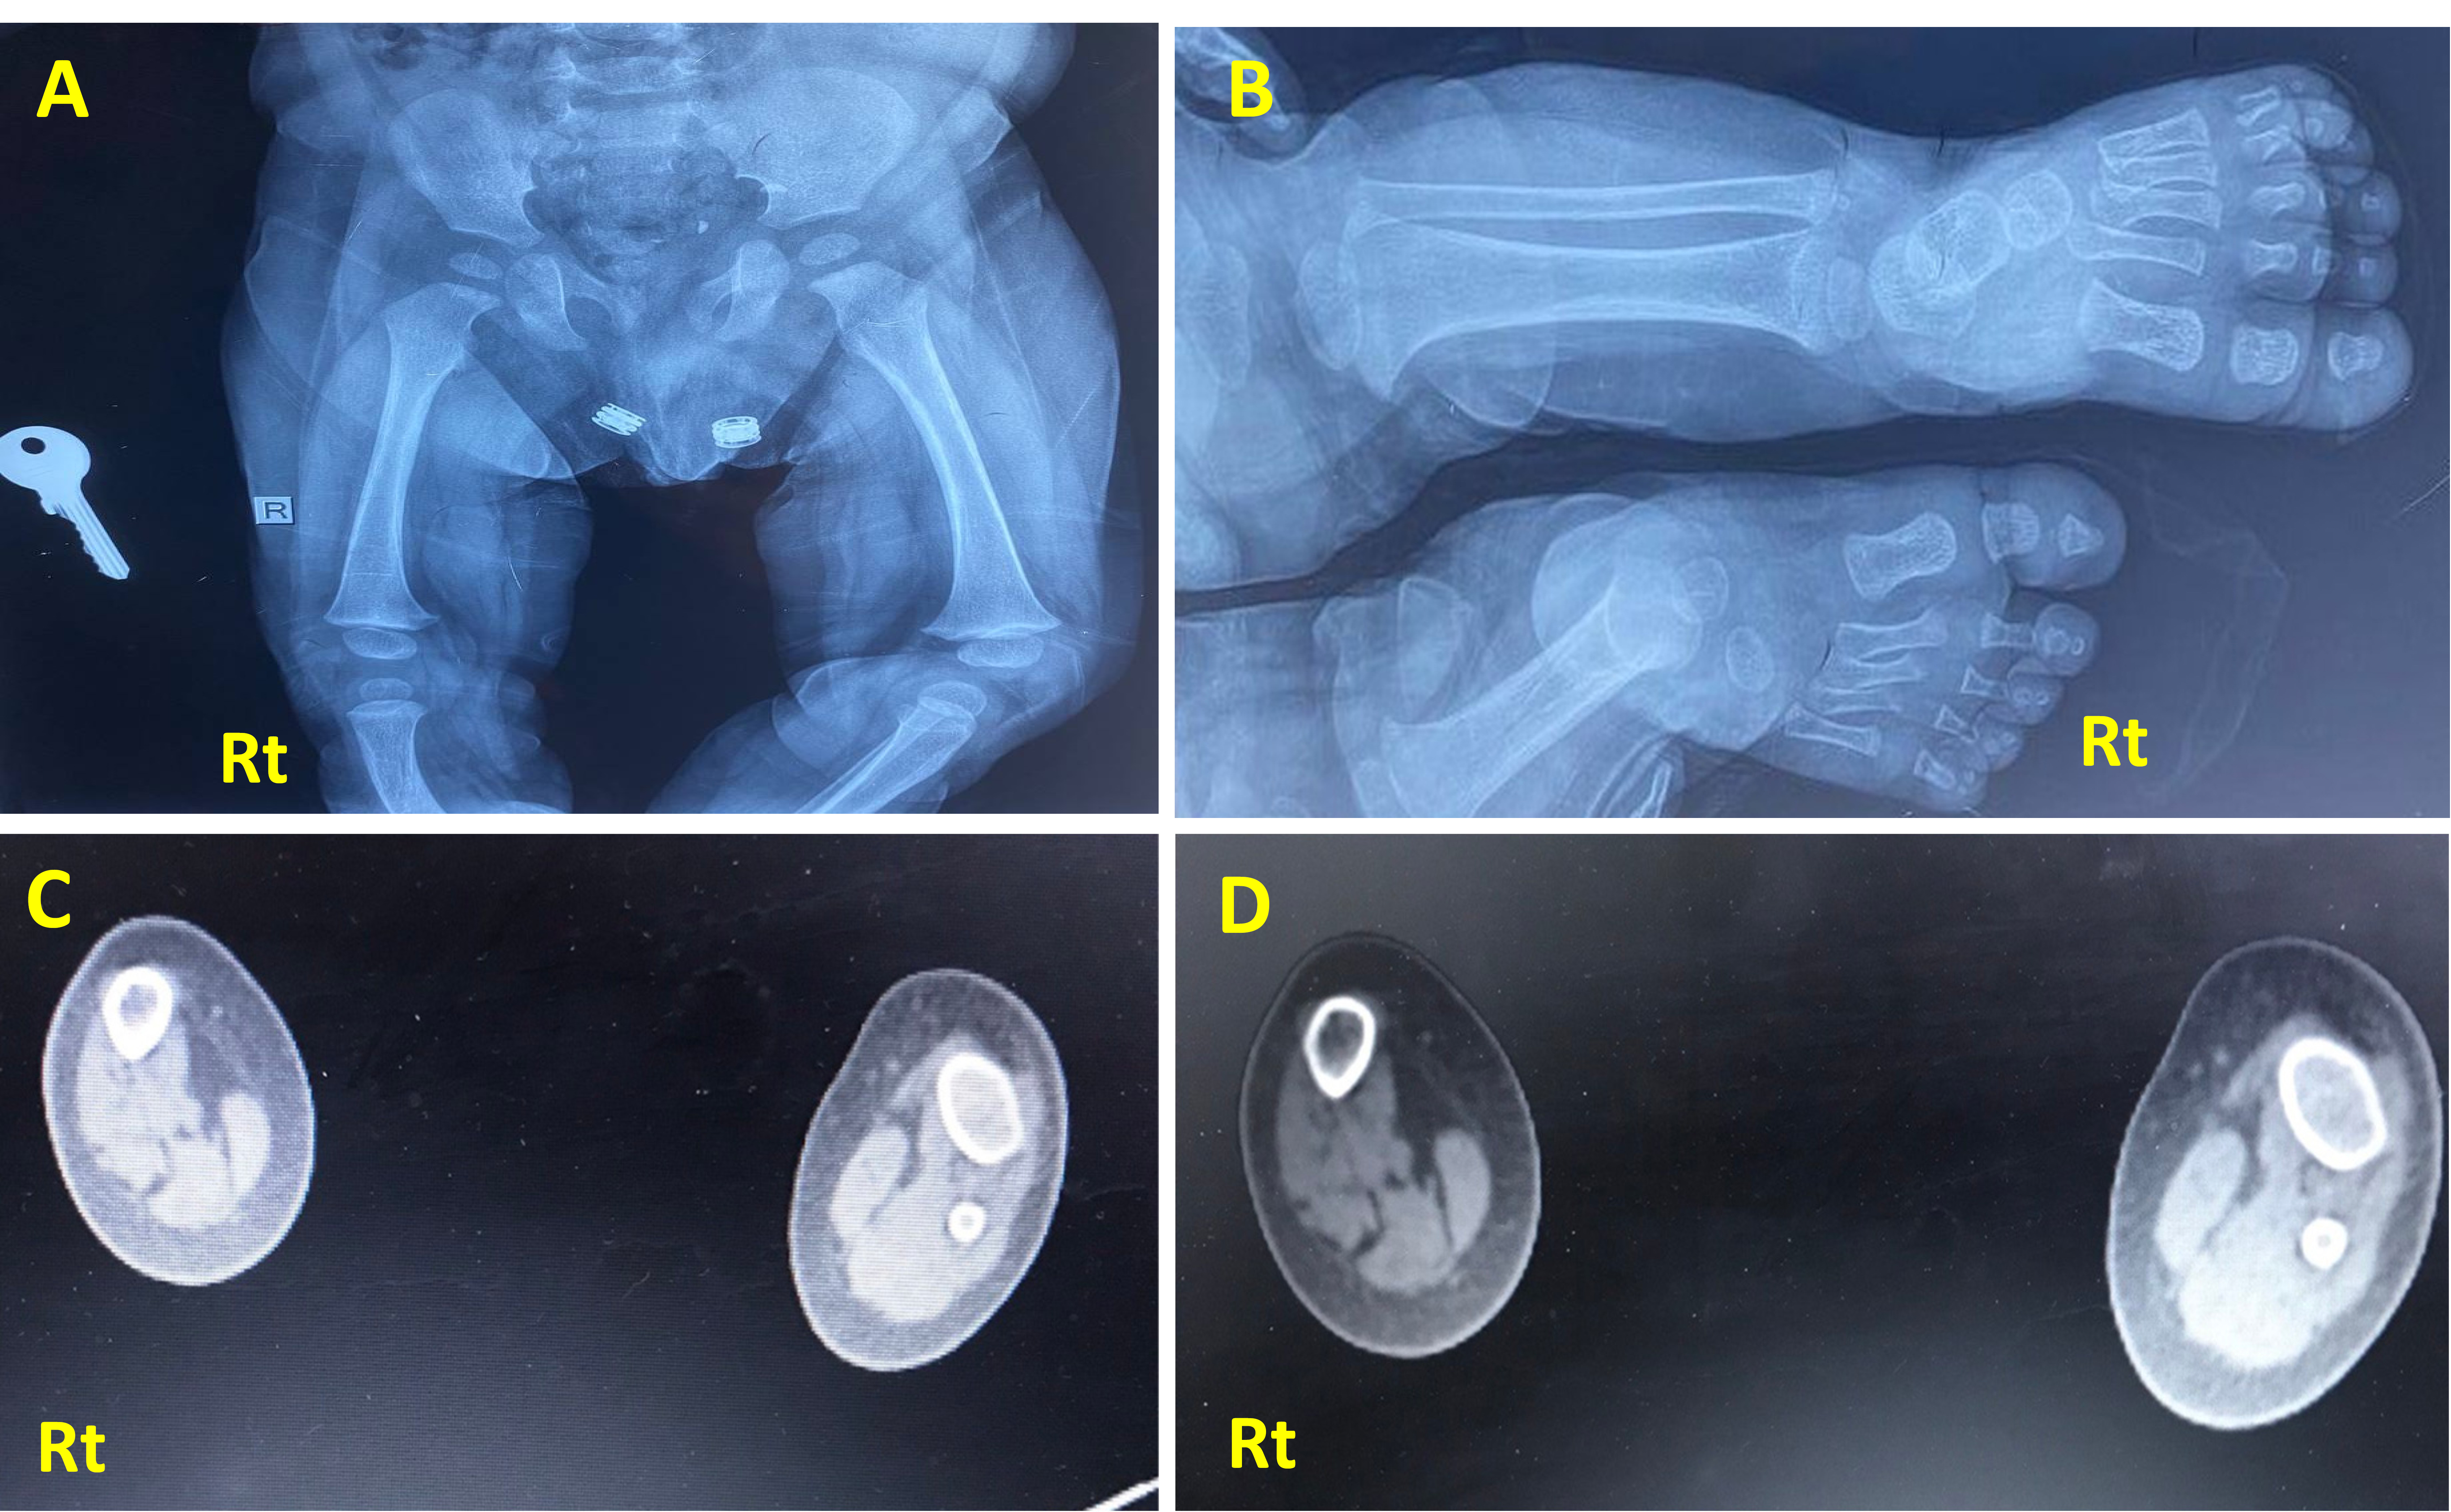

Imaging study, including X-rays (Figs. 2 and 3) and CT scans, confirmed the FH diagnosis and defined its severity. The case involved fibular hemimelia, characterized by fibular hypoplasia, a bowed tibia, and limb shortening, combined with proximal femoral focal deficiency (PFFD), in which the femur is shortened, angulated, or bowed, but demonstrates normal mineralization. PFFD tends to associate with FH in 50% of the cases [13, 14]. The ankle joint, foot, and tibia bone were unaffected. The diagnosis was consistent with type II FH with PFFD.

X-ray of the presented case. (A) Anteroposterior projection of both legs showing a completely absent Rt fibula with limb shortening and limb length discrepancy compared to the Lt side. The tibia is foreshortened, thickened, and bowed with medial rotation. (B) X-ray frontal view of Rt and Lt femur showing underdeveloped Rt femoral head compared to the Lt side, consistent with mild Rt proximal femur deficiency. (C, D): CT scan of both legs (axial section view) showing absent Rt fibula with deficiencies of the related muscular component, with the Rt tibia showing reduced radius compared to the Lt side.